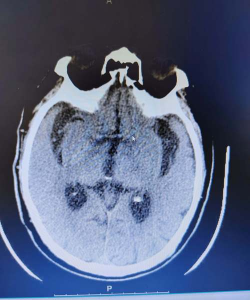

马的西尼罗河脑脊髓炎

脑脊髓炎是大脑和/或脊髓的炎症。西尼罗河病毒是西尼罗河脑脊髓炎的病因,于1999年首次在北美发现,尽管它在非洲、中东、西南亚和欧洲部分地区广泛分布。这种病毒性疾病主要由蚊子传播,其特征是中枢神经系统功能障碍,可能是致命的,或者可能导致疾病症